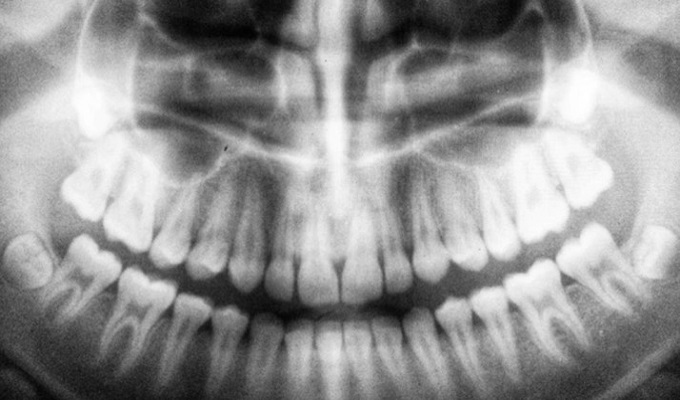

আক্ষরিক অর্থেই মহামারি নিয়ে বহু যুগ ধরে ‘ঘর করছে’ মানুষ। সেই সংক্রান্ত নানা তথ্য তুলে আনছে বিজ্ঞানেরই ভিন্ন একটি শাখা প্যালিওজিনোমিক্স। কার্যত বিপ্লব ঘটিয়ে দিয়েছে বিজ্ঞানের এই শাখাটি। মাটির তলা থেকে উদ্ধার হওয়া সাত পুরনো মাথার খুলি। সেই খুলির দাঁতে লুকিয়ে থাকা ডিএনএ (ডিঅক্সিরাইবোনিউক্লিক অ্যাসিড)-ই এখন মানবসভ্যতার রোগের ইতিহাস নতুন করে লিখছে।

মধ্যযুগে ইংল্যান্ডে হানা দিয়েছিল প্লেগ। সেই মহামারি ‘ব্ল্যাক ডেথ’ নামেই কুখ্যাত। কিন্তু তার আগেও মানুষ যে প্লেগের শিকার হয়েছিল তা এখন মানেন বিজ্ঞানী এবং প্রত্নতত্ত্ববিদরা। প্রস্তর যুগেই হানা দিয়েছিল প্লেগ। তার প্রমাণ মিলেছে সেই সময়ের কঙ্কালের দাঁতের টুকরো থেকে সংগ্রহ করা ডিএনএ-তেই। বহু যুগ পরেও সেই প্রমাণ নষ্ট হয়ে যায়নি। তবে সেই সময়ের প্লেগ এবং মধ্যযুগের প্লেগের জিনে কিছুটা ফারাক ছিল। মাছির শরীর থেকে ওই রোগ মানুষের দেহে আসার জন্য যে জিন প্রয়োজন তা প্রাচীন যুগের ব্যাকটেরিয়ার মধ্যে ছিল না। ওই রোগ ছড়াতো অন্য কোনও প্রাণী।